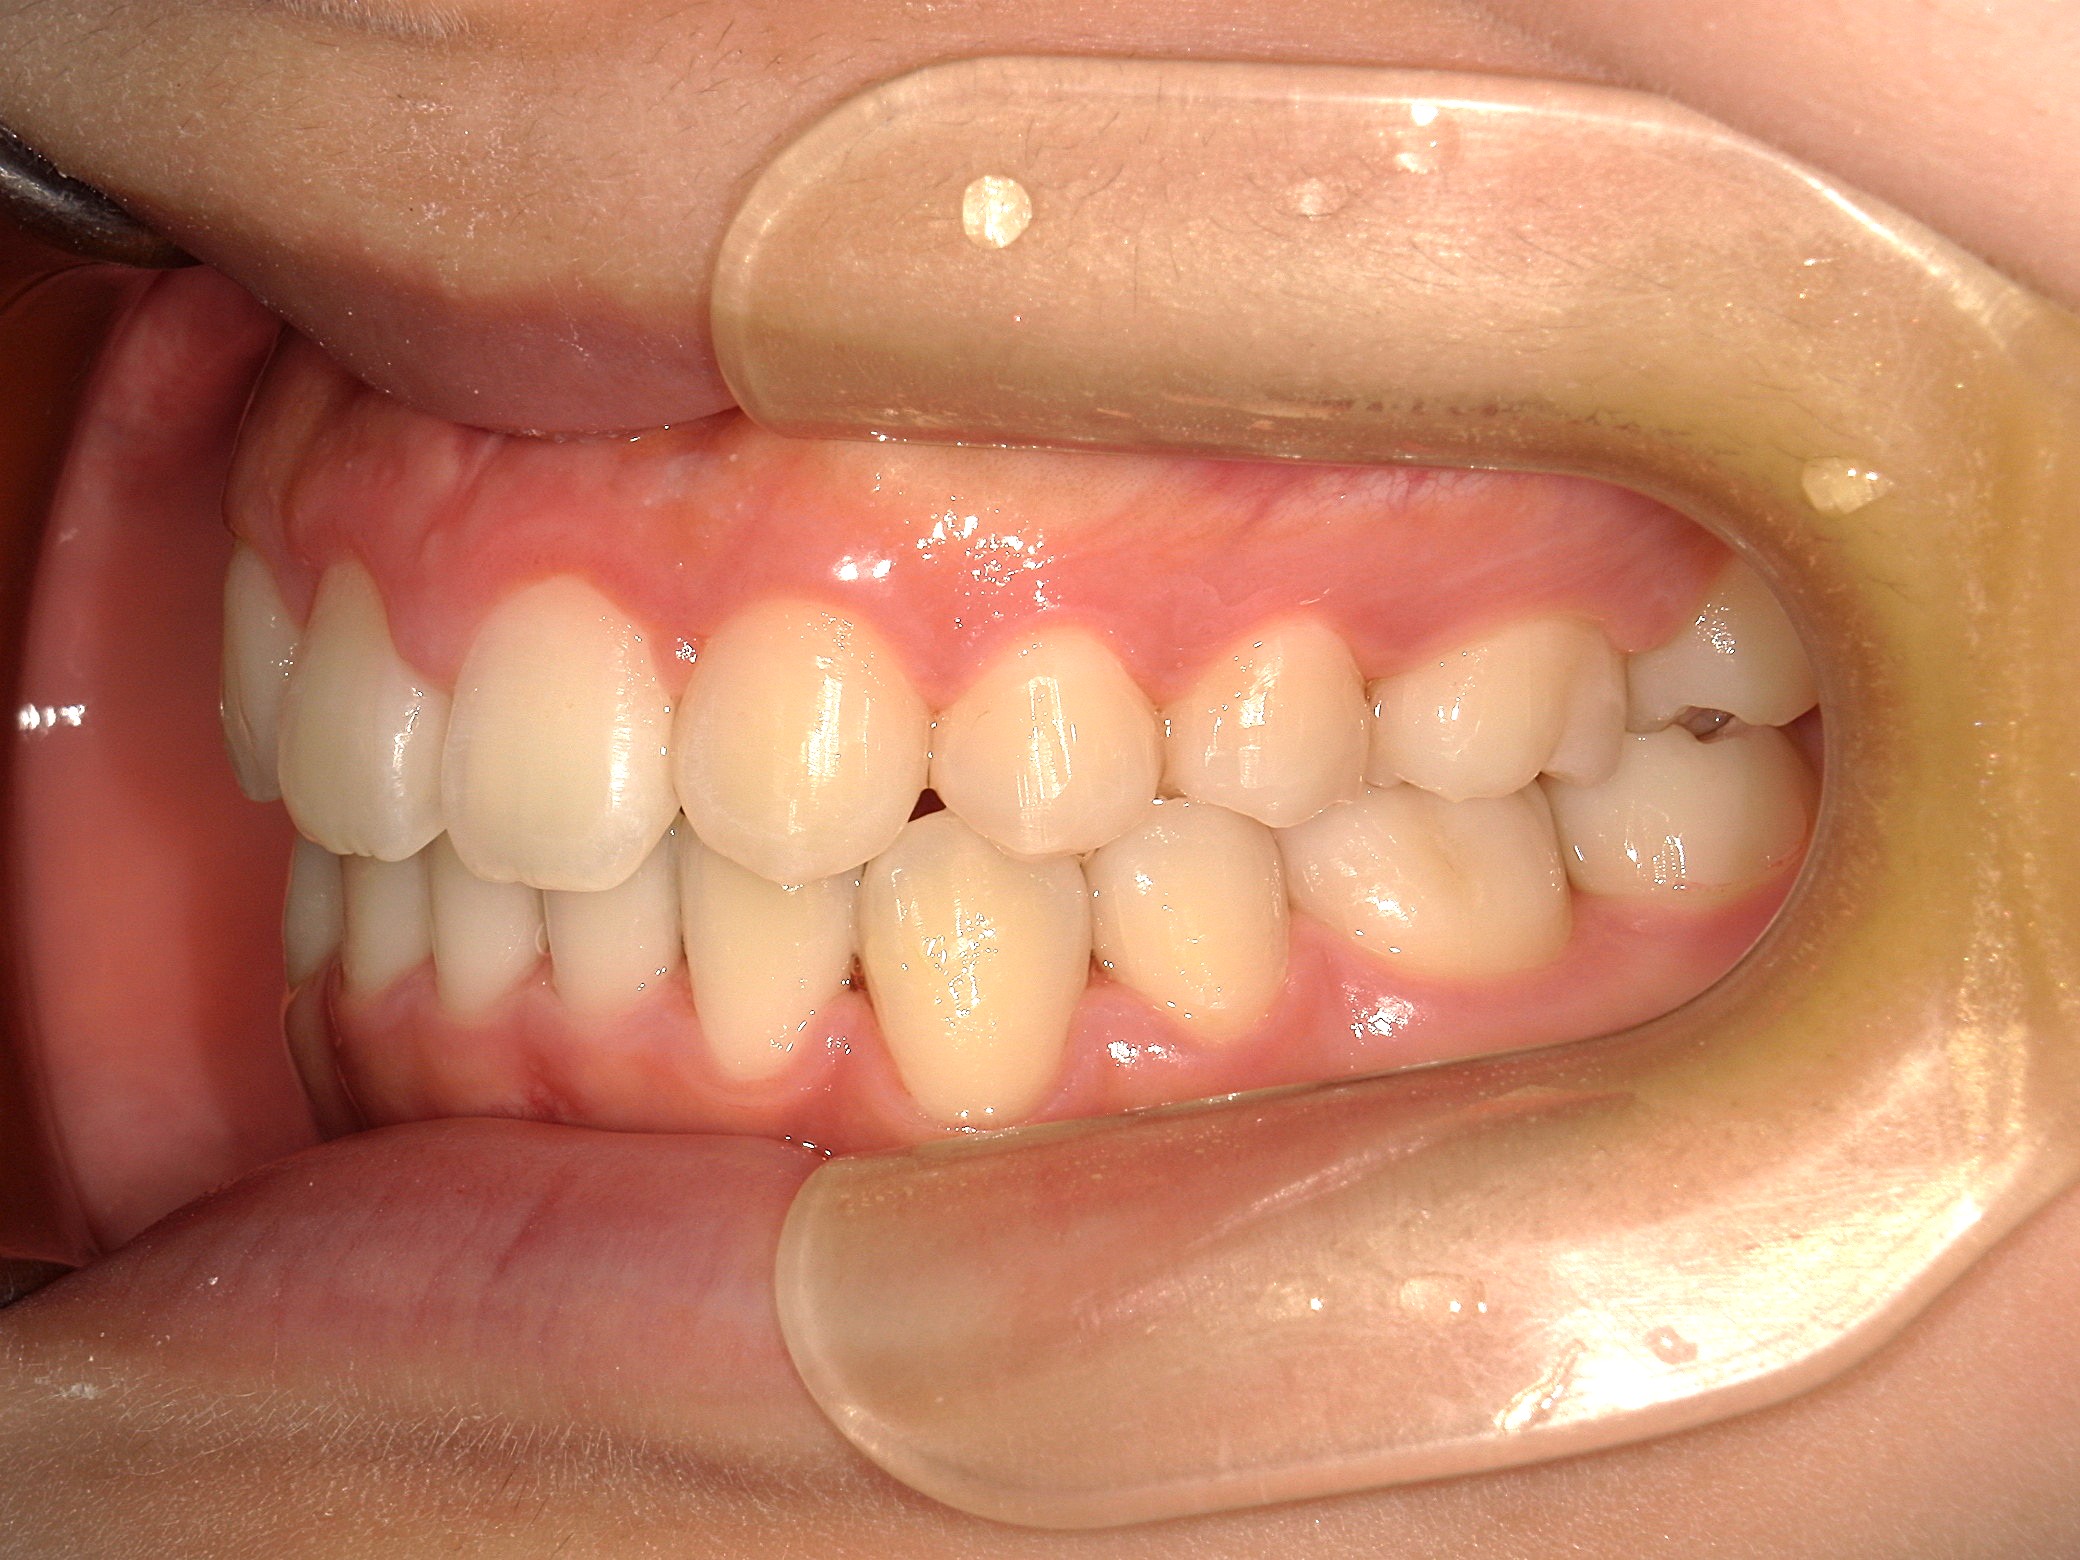

口内正面

治療前

上下の歯並びに凹凸があり、前歯の咬み合わせが深い状態でした。

また、上の前歯が2本、矮小歯(他の歯に比べて大きさが極端に小さい歯)でした。

歯を並べる隙間を作るため、上下共に歯を抜いて治療を行うこととしました。

上は矮小歯を、下は横の歯を抜いて治療を行いました。

上の歯は2番の歯を犬歯で代替しているので、上下の大きさの違いが出るのですが、不自然にならないよう幅をわずかに調節して仕上げています。